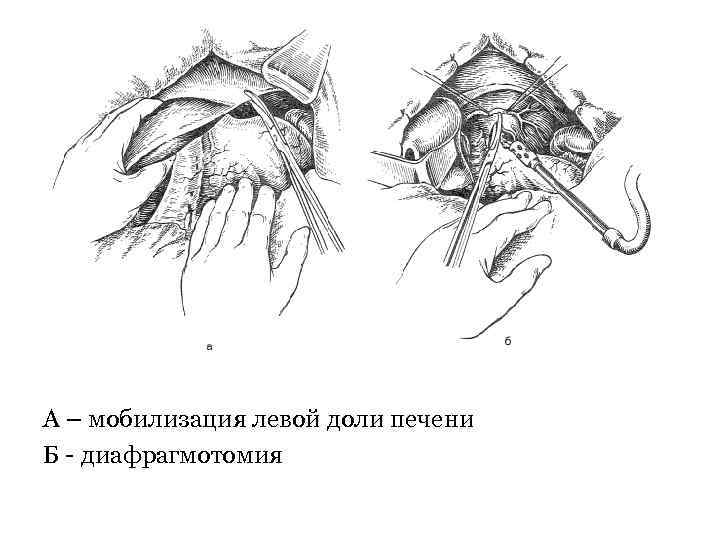

• Пищевод обходят указательным пальцем и берут на держалку. Выполняют саггитальную диафрагмотомию, пересекая кпереди сухожильную часть диафрагмы на протяжении 6 см.

• Пищевод обходят указательным пальцем и берут на держалку. Выполняют саггитальную диафрагмотомию, пересекая кпереди сухожильную часть диафрагмы на протяжении 6 см.

А – мобилизация левой доли печени Б - диафрагмотомия

А – мобилизация левой доли печени Б - диафрагмотомия